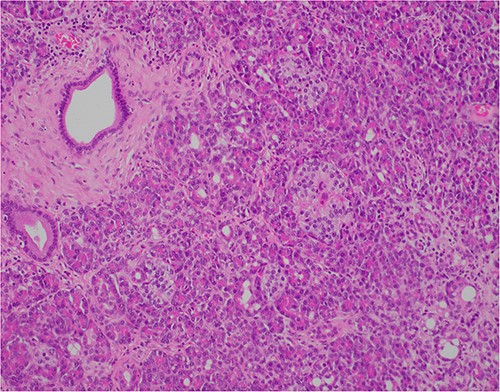

At outpatient phone clinic review 2 months post-surgery, the patient had recovered well, and his pre-operative symptoms of nausea, vomiting and pain had completely resolved. The histopathology of the gallbladder found chronic cholecystitis with cholelithiasis, in addition to a 6 mm focus of pancreatic heterotopia in the gallbladder wall. This heterotopic tissue contained acini, ducts and islet cells, classifying it as Type I pancreatic heterotopia (Figs 1–3).

×20 objective lens; normal duct towards left hand side; acini (with dense pink cytoplasmic granules) and islets (clusters of pale cells).